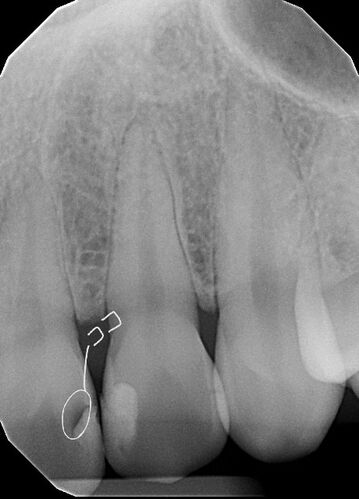

今日で最後の予定の歯医者へGO。 2時にバイトを終わらせて近くのフードコートで時間潰して3時頃歯医者へ。 今日は神経の先生がいないのでオーナーの?先生で。 日本人のアシスタントは今日はお休みでした。 神経には薬が詰まってるのでレジンの蓋をして。 …